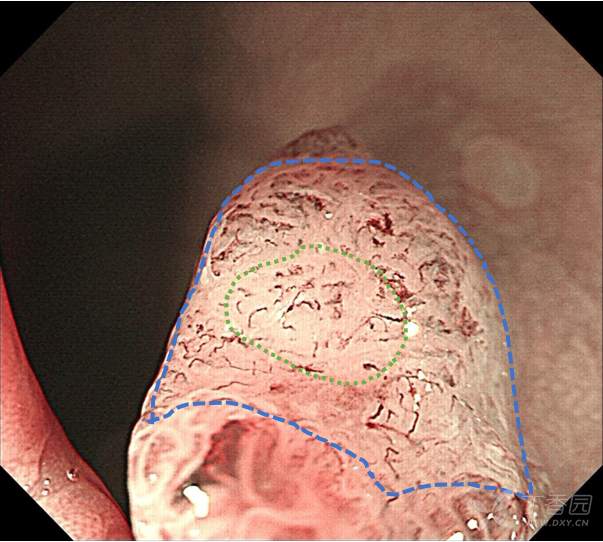

专注早癌诊断,从整体形态到微观表面,详细的判断:JNET、Pit pattern、浸润深度?

这是在跟老师发现的一例病人,在发现病人之后,通过不同的方法,比如NBI、放大、化学染色,对这个病变通过不同的角度,从宏观到微观细致的观察,详细的分析,以便于大家能够更好的理解:

一、pit pattern 分型的实际具体的形态是什么样子的?

二、JNET分型的特点和细微差别又是什么?

三、不同形态的病变,不同的分型的相应形态下对应的病理状态是什么?